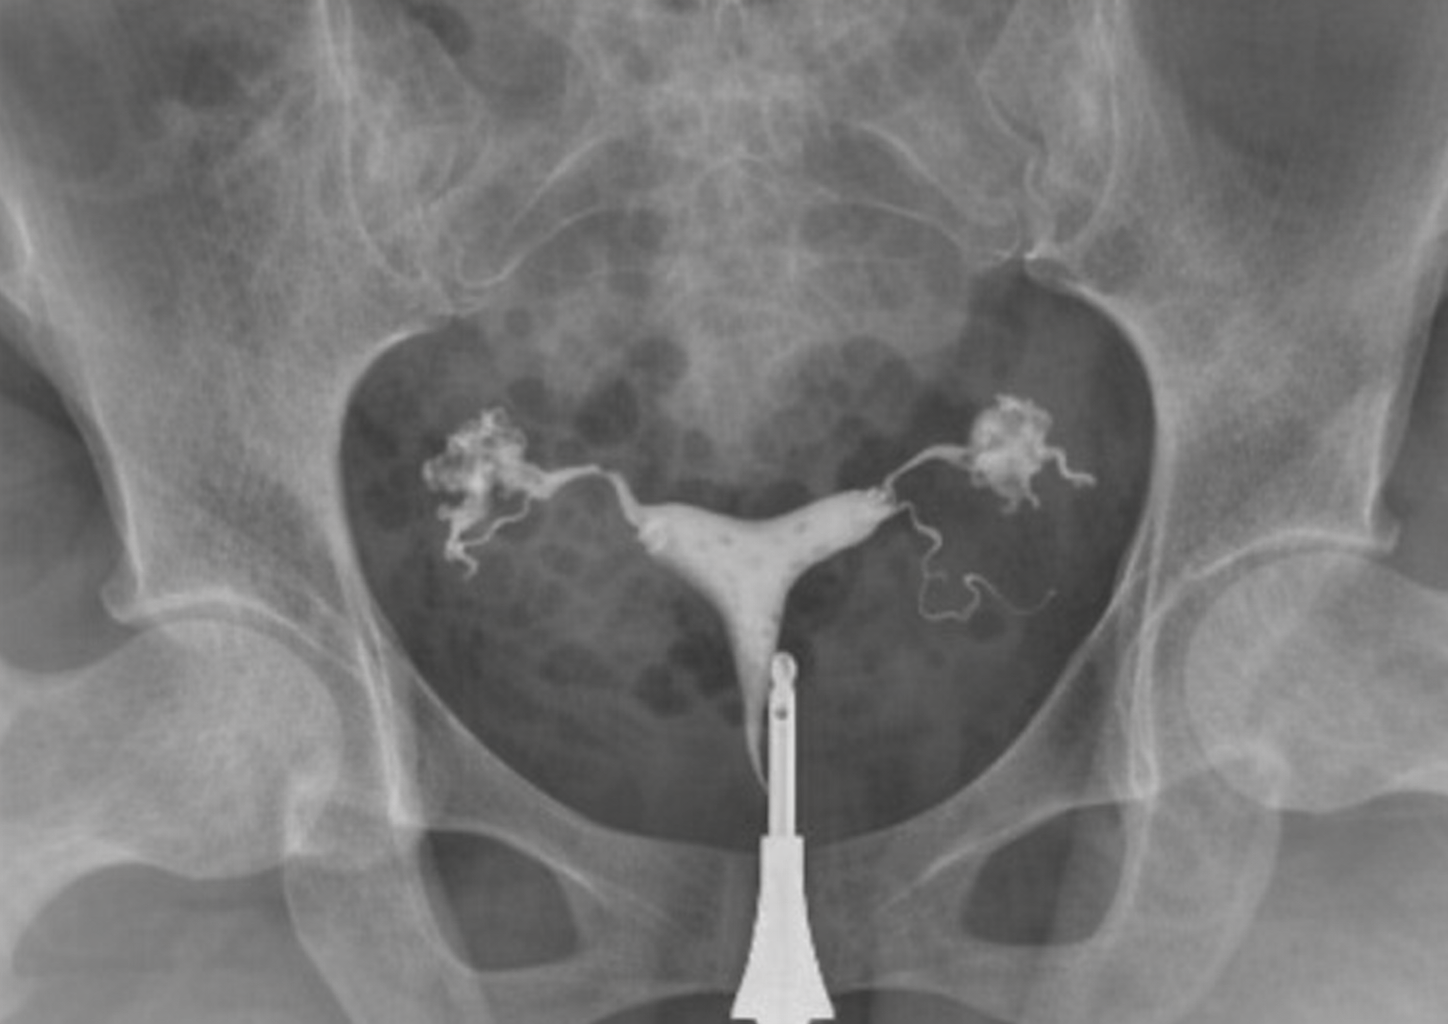

Hydrosalpinx is a condition in which the fallopian tubes become filled with fluid. It usually occurs as a result of previous infections, pelvic inflammatory diseases, or damage to the tubes. This condition can impair the normal function of the tubes and make it more difficult to achieve pregnancy.

In the presence of hydrosalpinx, the fluid accumulated inside the tube may occasionally flow back into the uterus. This fluid can prevent the embryo from implanting in the uterine wall and can significantly reduce success rates, especially in IVF treatments. Therefore, treatment planning is of great importance in patients diagnosed with hydrosalpinx.